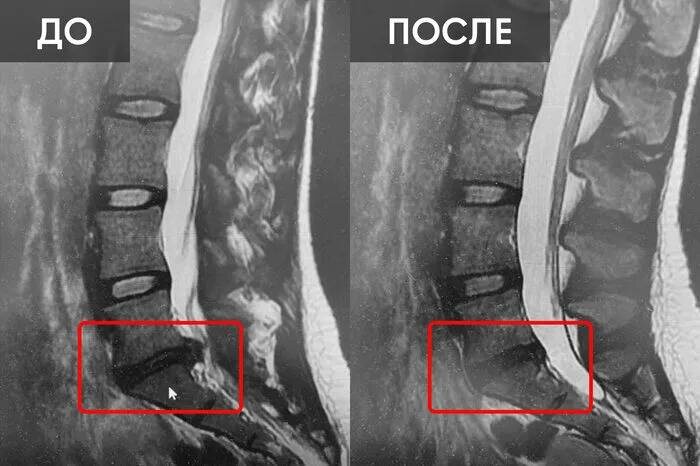

Мужчина — 42 года, офисная работа, долгие годы — сидячий образ жизни. Около года назад начались прострелы в пояснице, которые отдавали в ногу: сначала редкие, потом всё чаще. Наконец сделали МРТ — подтвердили грыжу межпозвоночного диска L4–L5.

Заключение: есть показания и на операцию, и на консервативное лечение — многое зависит от динамики и индивидуальных симптомов.

Пациент выбрал сначала попробовать восстановиться без операции. В течение шести месяцев работал с мануальным терапевтом и самостоятельно прорабатывал проблемную зону дома по рекомендованной методике CORDUS SACRUS. Регулярные сеансы мобилизации, мягкотканые техники, упражнения на укрепление центра тела, нейродинамические (скользящие) упражнения для нерва, и сильный акцент на изменении ежедневных привычек — как сидеть, как спать, как распределять нагрузку - помогли. Постепенно боли уменьшились, прострелы стали редкими, мужчина вернулся к плаванию и длинным прогулкам. Сегодня пациент не думаю о грыже каждый день — она есть, но перестала доминировать в его жизни.